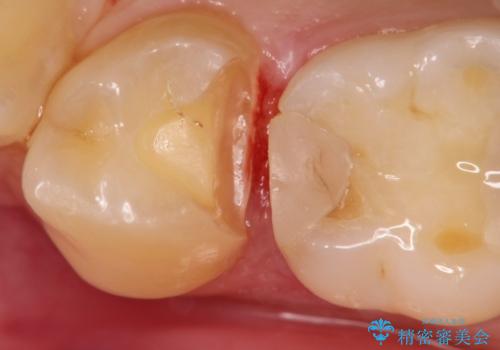

【セラミックインレー】虫歯の治療

- 定期検診にてむし歯を認めたため、セラミックインレーにて修復を行いました。

e-max プレスインレーにて修復治療を行っているため適合性及び審美性の高い治療を行うことができます